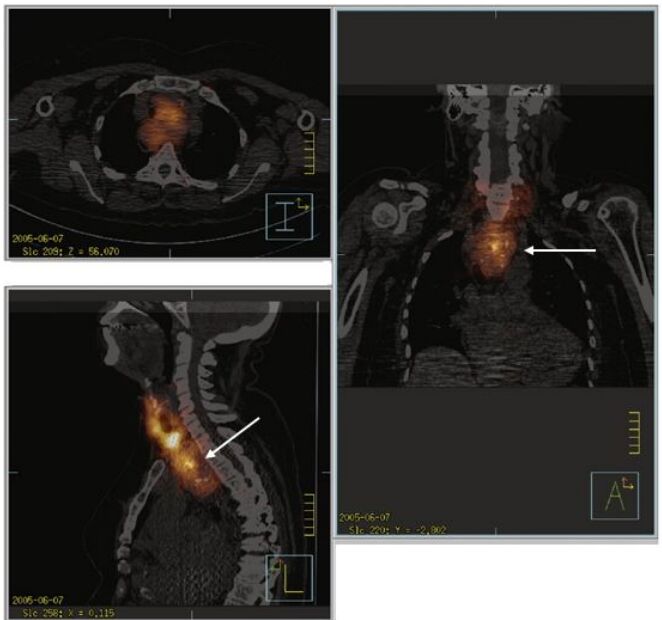

41.123I-NaI甲狀腺之單光子電腦斷層造影與電腦斷層融合影像(如下圖),箭頭所指最可能為何? (圖I:橫向面影像,圖L:縱向面影像,圖A:冠狀面影像)(A)脊椎甲狀腺 (B)舌下甲狀腺 (C)上縱膈腔甲狀腺 (D)頸部甲狀腺